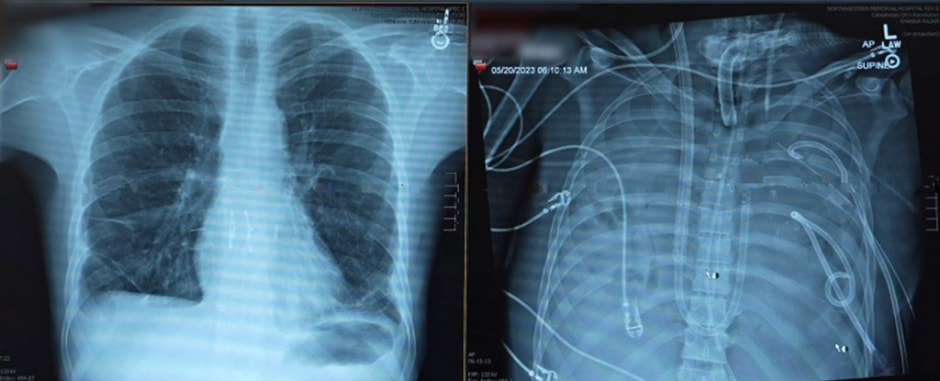

На протяжении 216 часов — это девять полных суток — свиное лёгкое не только сохраняло структуру, но и выполняло функции газообмена. Это означало, что, несмотря на межвидовой барьер, орган оказался достаточно совместимым. Однако уже через сутки после пересадки у пациента началось воспаление, схожее с так называемой первичной дисфункцией трансплантата. К третьему дню были зафиксированы признаки отторжения, но к девятому дню врачи наблюдали частичное восстановление лёгочной ткани.

Важно отметить, что ни гиперострой реакции, ни инфекций обнаружено не было. Пациент получал сильнейшую иммуносупрессию, включающую восемь различных препаратов, в том числе антитела, стероиды и ингибиторы цитокинов. Несмотря на сложный фон, пересадка дала уникальный результат: орган не был немедленно разрушен.